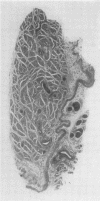

A study was made of the sartorius muscle in Jamaican infants dying of protein malnutrition. Total counts were made of muscle fibres and sub-sarcolemmal nuclei in transverse section and compared with controls.

A striking pathology is found in severe cases. The muscle fibre is reduced to a size comparable with that of the foetus. Although there is a greatly increased concentration of cells, there is also degeneration and actual loss of fibres and of sub-sarcolemmal nuclei. The proportion of the area occupied by muscle bundles may be halved, and there is a marked relative increase in interstitial collagen.